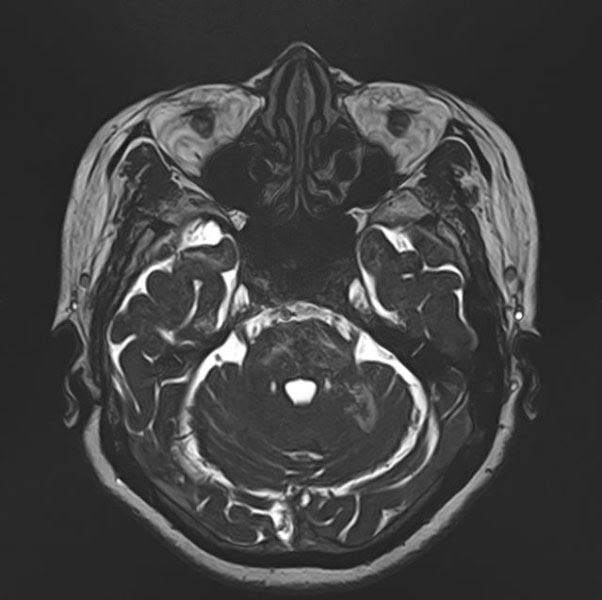

手術前

(MR1)